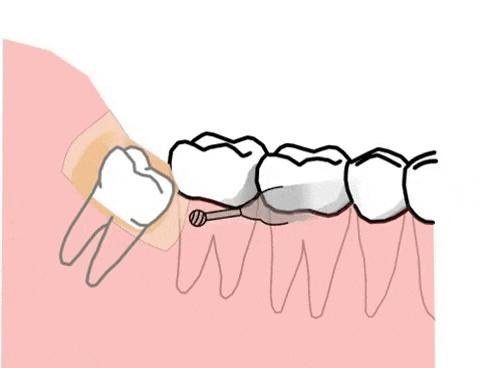

一般埋伏牙的处理方式有两种:一是直接拔除,另一种是通过正畸牵引。

直接拔除的情况一般是针对长得歪斜奇怪,有可能会影响正常牙齿健康的才会考虑拔除,如埋伏智齿,影响邻牙健康的话一般都会建议拔除。

正畸牵引的话,这种情况一般是由于埋伏牙是在正常的牙齿数量中。毕竟我们每颗恒牙都十分珍贵,一般牙医是不建议拔除正常的牙齿的。